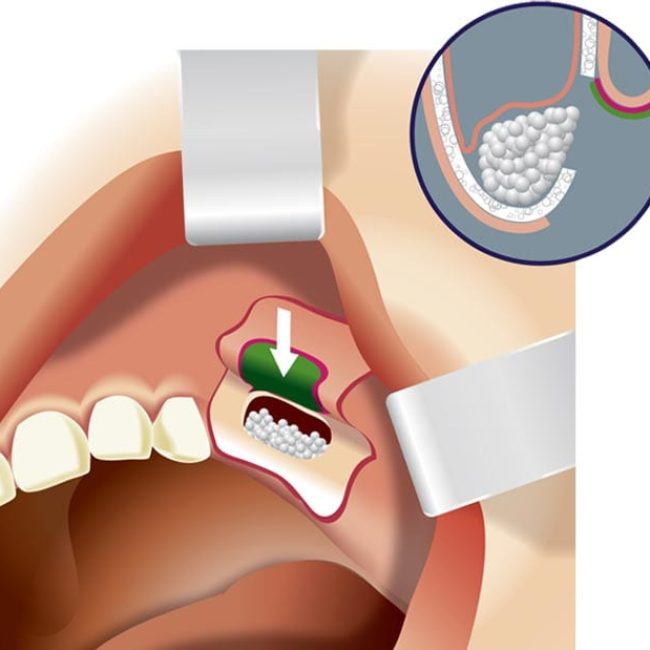

הרמות סינוס פתוחות + סגורות, השתלות עצם

הרמת סינוס הינה פעולה כירורגית המתבצעת עקב אובדן וחוסר עצם בלסת העליונה, והיא מיועדת לצורך הגבהת העצם הקיימת, על מנת להכין קרקע אופטימלית להשתלת שיניים מוצלחת. במהלך הרמת הסינוס, דוחקים את רירית הסינוס כלפי מעלה, ויוצרים חלל בינה לבין רצפת הסינוס הקשה. את החלל שנוצר ממלאים בתחליף עצם..